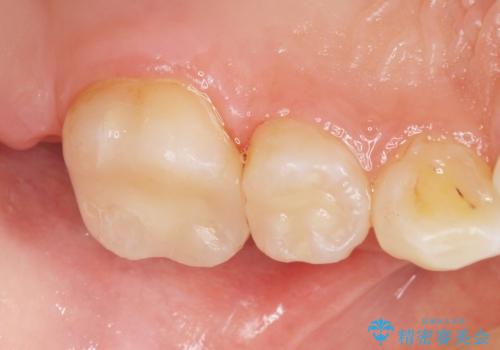

う蝕を丁寧に除去したのち、セラミックインレーによる修復を行いました。

セラミックインレーの審美的な仕上がりと自然な咬み心地にご満足頂けました。

「フロスを通したときの嫌な臭いもなくなった」と喜んで下さいました。

インレーの種類:セラミックインレー(e-max press)